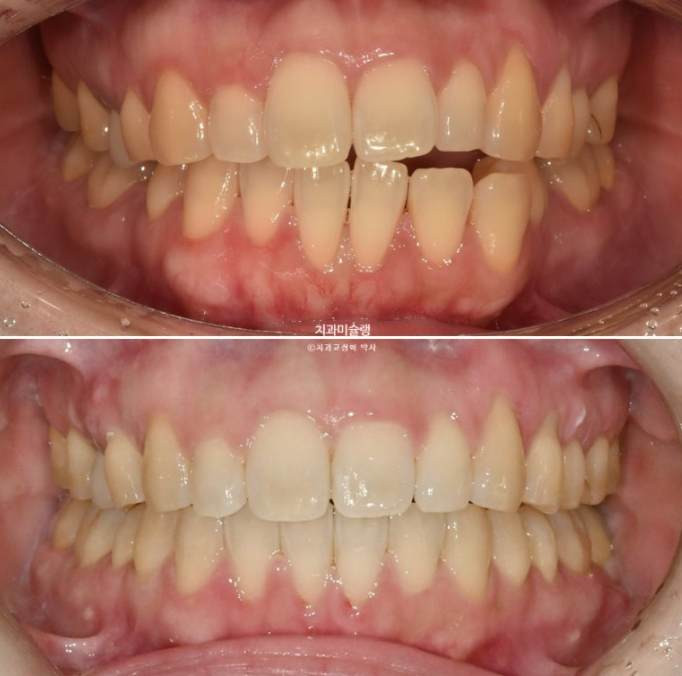

이제 안모비교해보겠습니다.

24.06~25.11

윗니 아랫니 수평 간격이 줄어들며 입술부전증이 해소가 되었습니다.

윗니 돌출 해소로 깔끔해진 스마일

윗니 뻗침이 줄어들어 아랫니 간격이 줄어들며 입술이 자연스럽게 다물리게 되었습니다